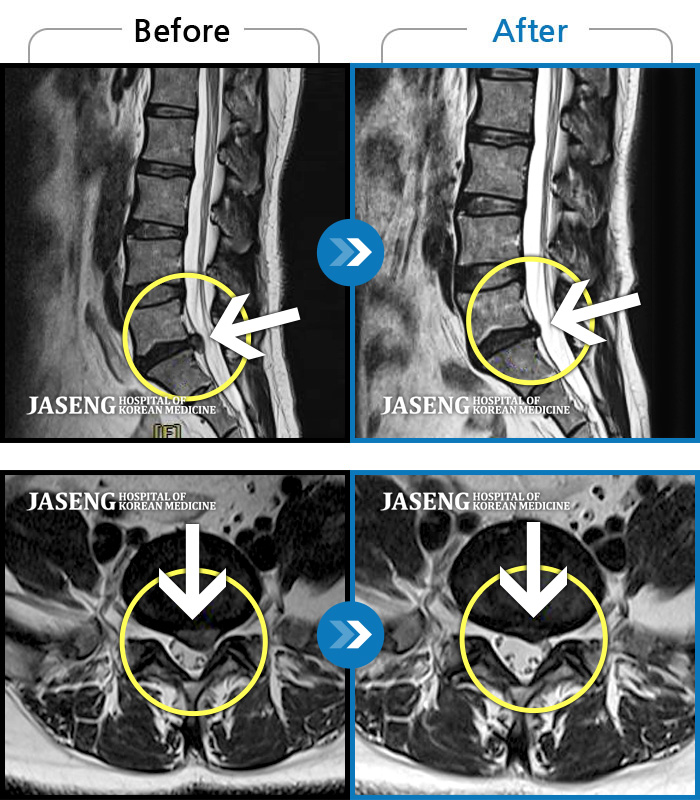

허리디스크

도움받은 사례

광주 · 장영우 원장

양측 허리부터 좌측 다리까지 이어지는 저림과 통증으로 걷기 힘들어 내원하였습니다.

촬영시기

2024.11.22 ~ 2025.05.16

2025.05.30

조회수 284